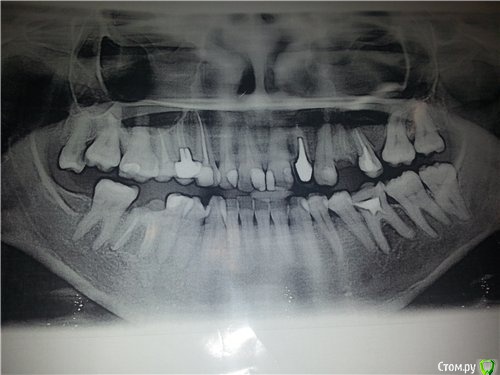

Лана* Опубликовано 1 января, 2016 Автор Поделиться Опубликовано 1 января, 2016 (изменено) С новым годом! обещала картинку зубок.буду рада услышать советы по протезированию. Низ 6 ка уже с коронкой, сделала. Верх 8 ка удалена. Изменено 1 января, 2016 пользователем Лана* Ссылка на комментарий

IvanK Опубликовано 13 января, 2016 Поделиться Опубликовано 13 января, 2016 Консультация ортодонтаУдаление 18, 24, 46?Повторное лечение, протезирование 12, 11....15, 14?, 13,22, 25, 36, 46, Имплантация 24, 46? 1 Ссылка на комментарий

red_butler Опубликовано 13 января, 2016 Поделиться Опубликовано 13 января, 2016 Я бы и 2.5 убрал 1 Ссылка на комментарий